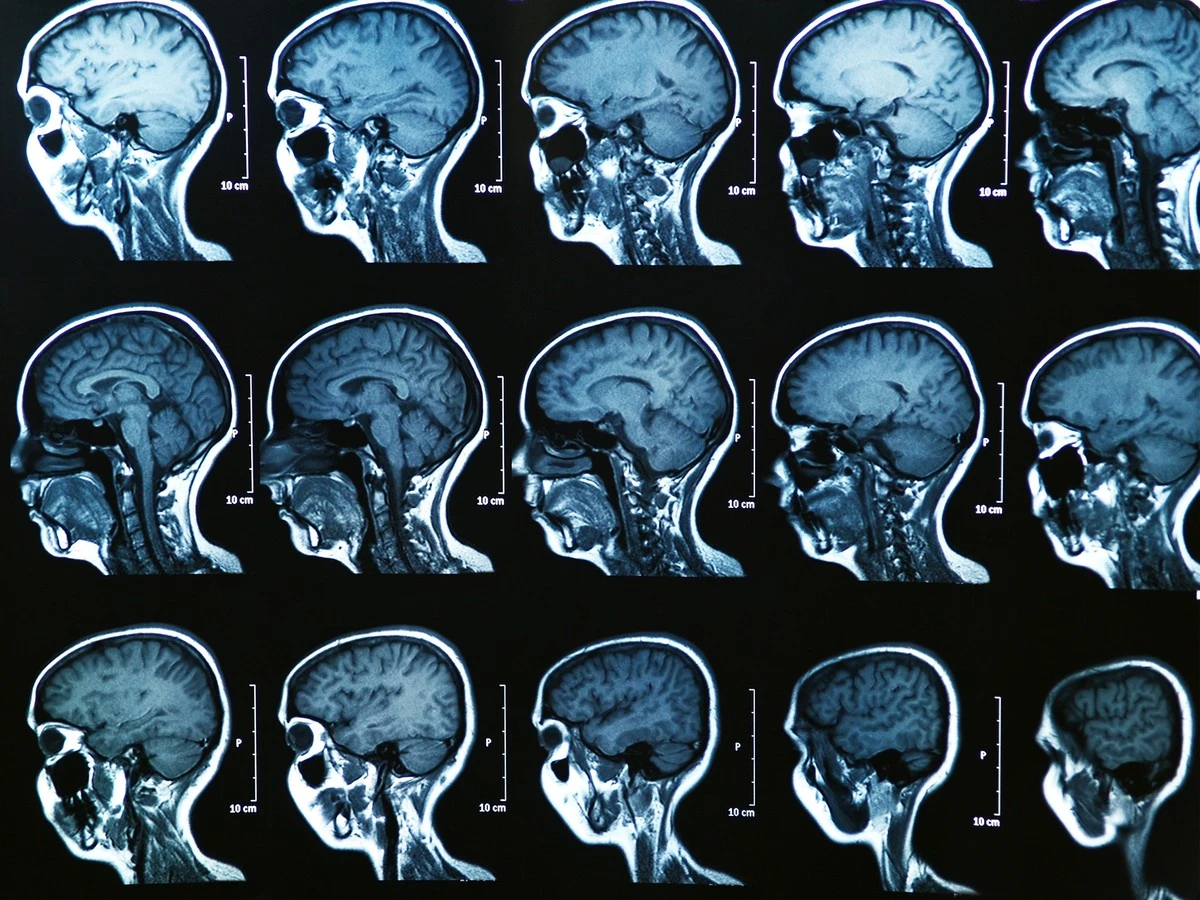

Die tiefgreifende Analyse: Magnetresonanztomografie (MRT)

Wenn es um die Darstellung von Weichteilen geht, ist das MRT oft unschlagbar. Entzündungen, Verschleißerscheinungen, Tumore – das MRT liefert hier besonders präzise Ergebnisse. Anstelle von Röntgenstrahlen nutzt es ein starkes Magnetfeld und Radiowellen. Ihr Körper wird in eine Röhre gefahren, und die Anordnung von Wasserstoffatomen in Ihrem Körper wird gemessen.

Vorbereitung ist alles: Da ein starkes Magnetfeld im Spiel ist, müssen vor der Untersuchung alle metallischen Gegenstände abgelegt werden – von Brillen und Schmuck bis hin zu Herzschrittmachern oder Metallimplantaten. Diese müssen unbedingt im Vorfeld mit dem Arzt besprochen werden! Die Untersuchung ist allerdings laut, weshalb Sie Ohrstöpsel erhalten und bei Platzangst ein beruhigendes Mittel bekommen können.

- MRT: Weichteile, Gehirn, Gelenke, Tumore. Sehr detailliert, keine Strahlenbelastung, aber zeitaufwendiger und mit Einschränkungen bei Metall.